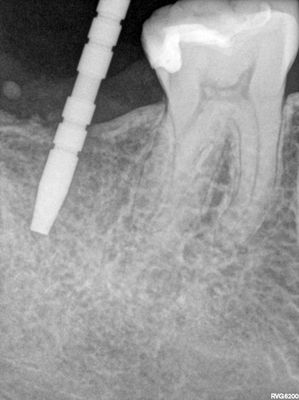

JYeung - 47 implant

Soft bone, some repositioning required due to distal slant of anterior tooth roots. Good end positioning